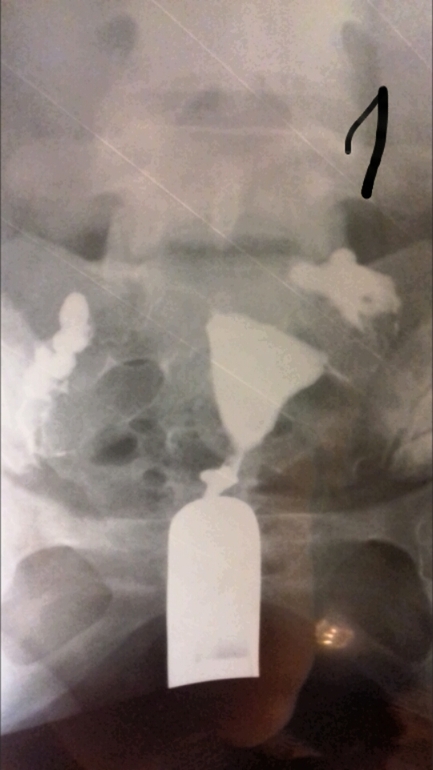

ГСГ помогите расшифровать.

ГСГ, ЭХО, МСГ, ФертилоскопияВсем привет. Кто понимает в снимках. Сделала гсг. На третьем сказали жидкость вышла, но как-то долго она выходила и спайки видно, поставили эндометриоз и спаечный процесс в брюшной полости. Беременность не наступает и стимуляции были. В 2006 году было кесарево и в 2012 прижигали эррозию ш/м, больше ничего.